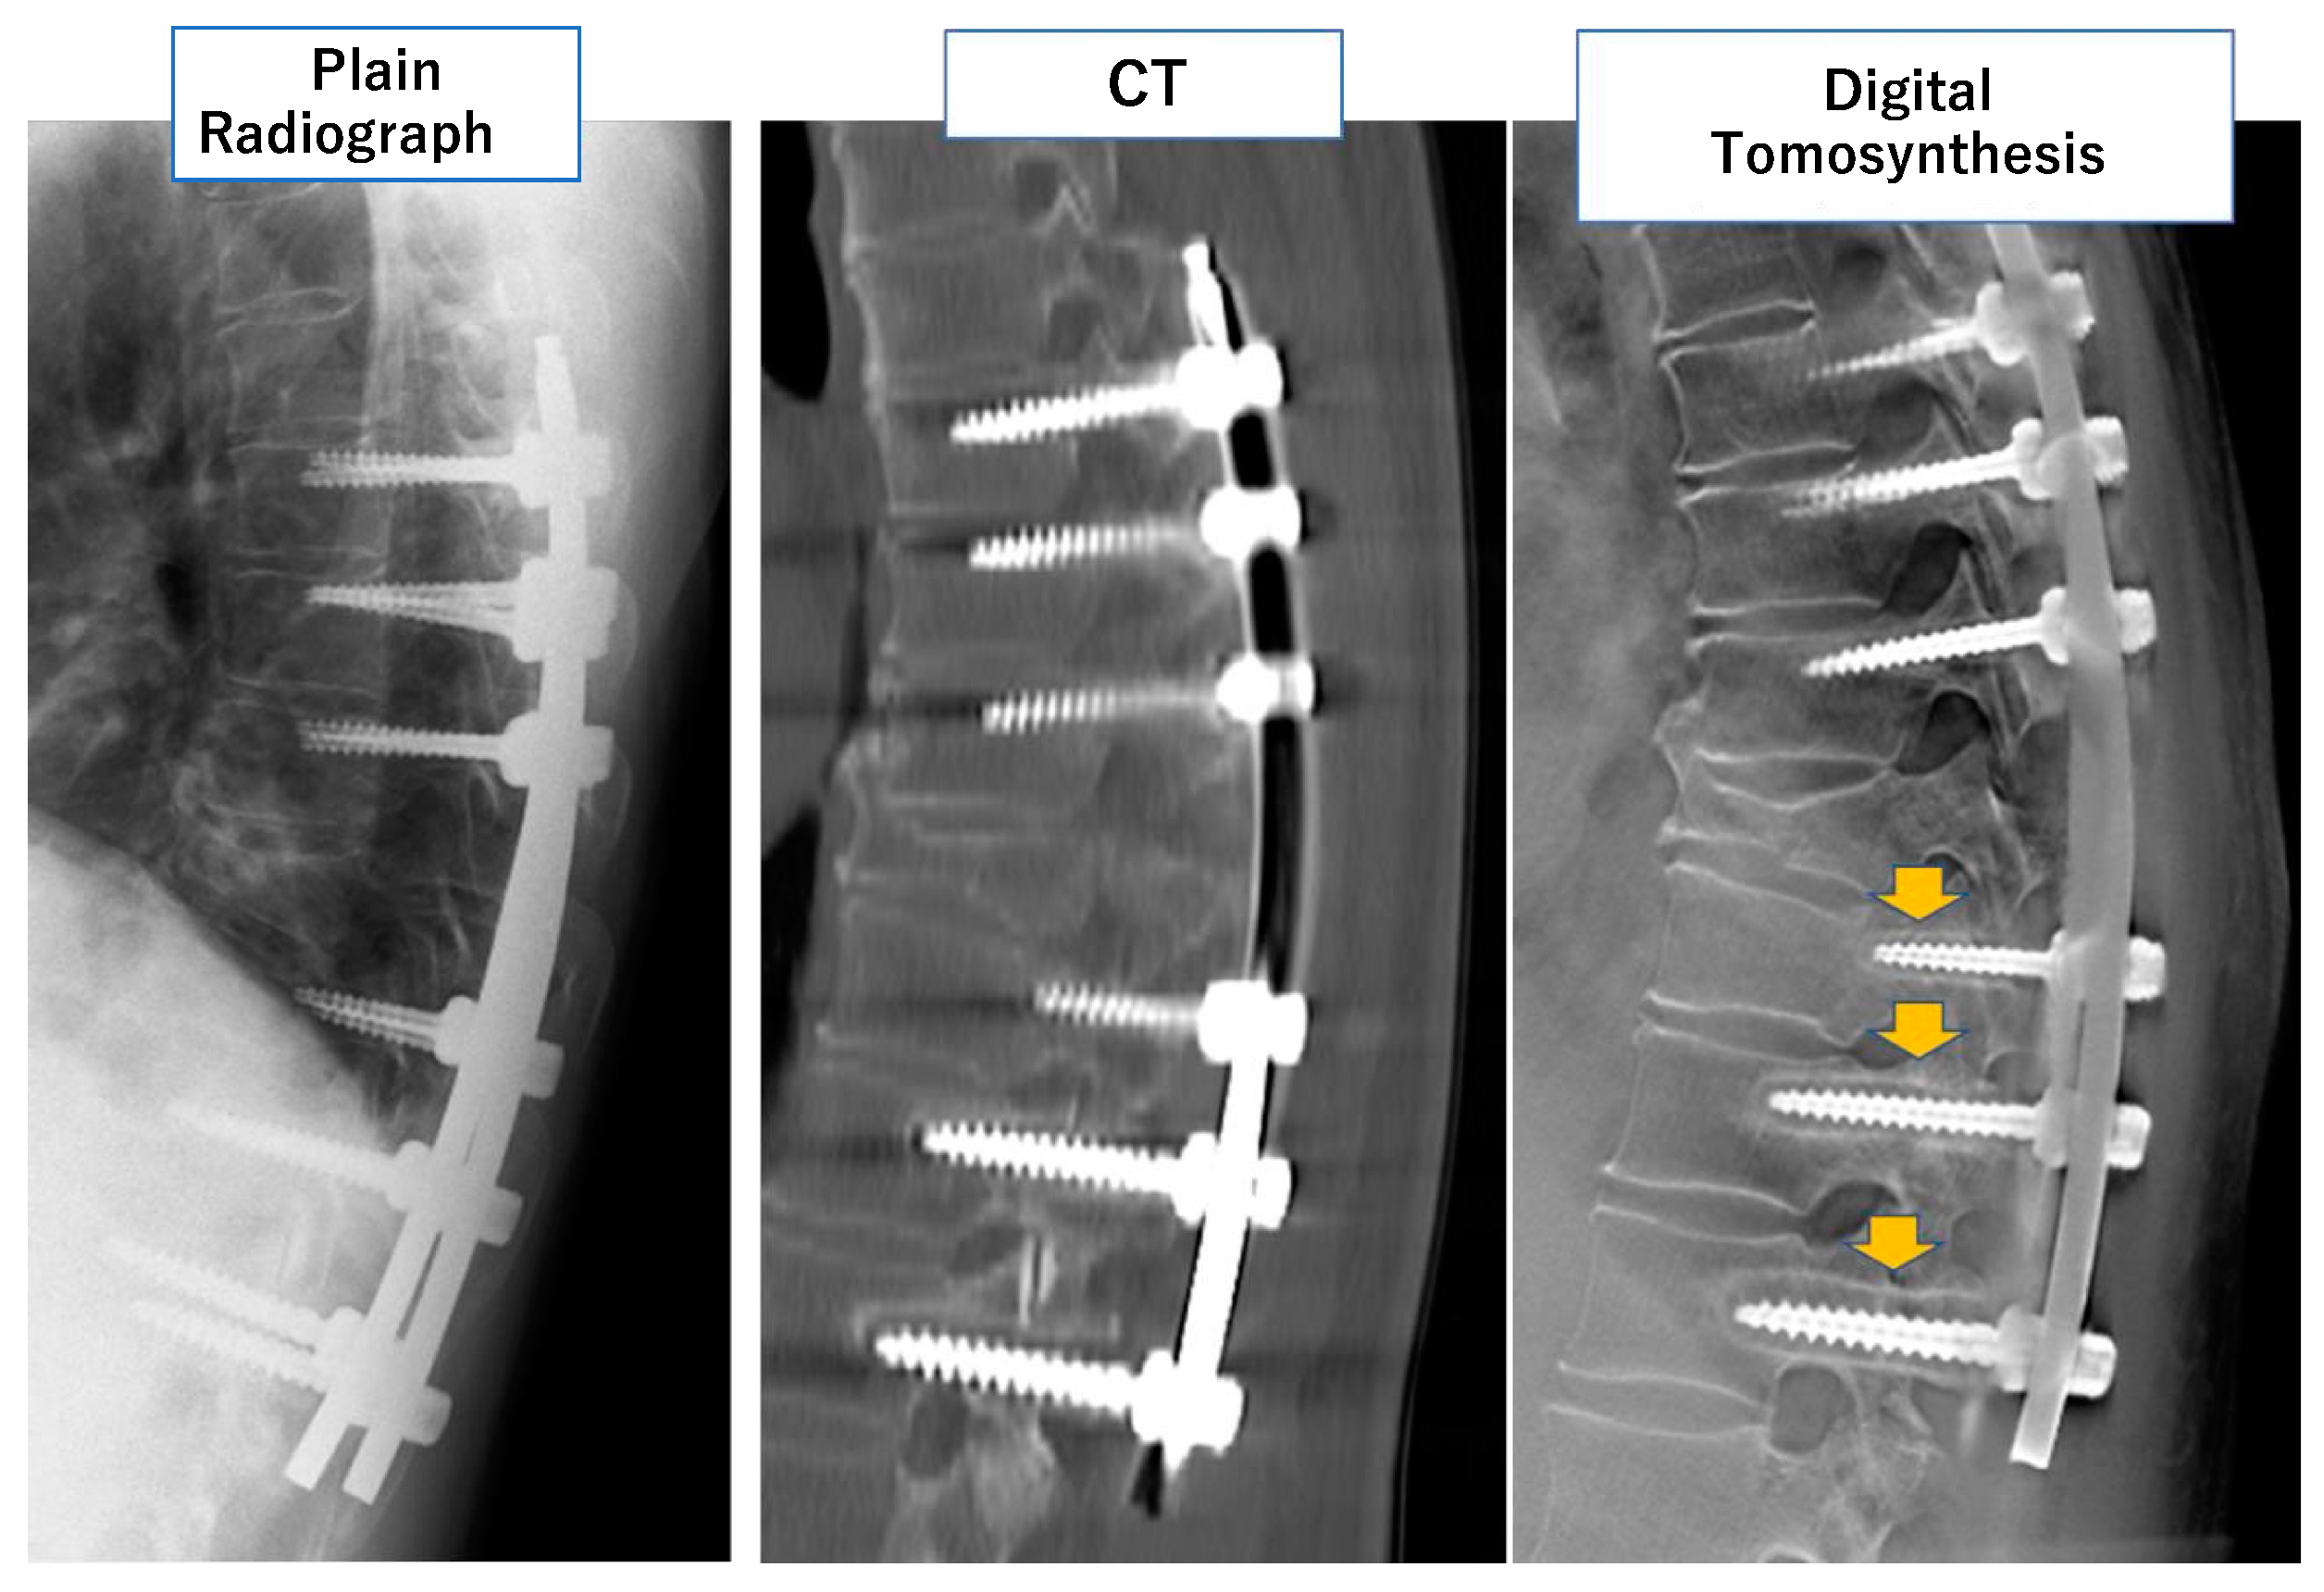

- Okano, E.; Hara, Y.; Ito, A.; Mataki, K.; Totoki, Y.; Noguchi, H.; Nagashima, K.; Matsumoto, Y.; Yanagisawa, Y.; Mutsuzaki, H.; et al. Novel method for selecting slices of the same cross-sectional view from digital tomosynthesis for monitoring posterior spinal instrumentation. J. Clin. Neurosci. 2021, 92, 183–188. [Google Scholar] [CrossRef] [PubMed]

- Mataki, K.; Hara, Y.; Okano, E.; Nagashima, K.; Noguchi, H.; Shibao, Y.; Miura, K.; Takahashi, H.; Funayama, T.; Koda, M.; et al. Development of a quantitative method to evaluate pedicle screw loosening after spinal instrumentation using digital tomosynthesis. BMC Musculoskelet. Disord. 2022, 23, 35. [Google Scholar] [CrossRef] [PubMed]